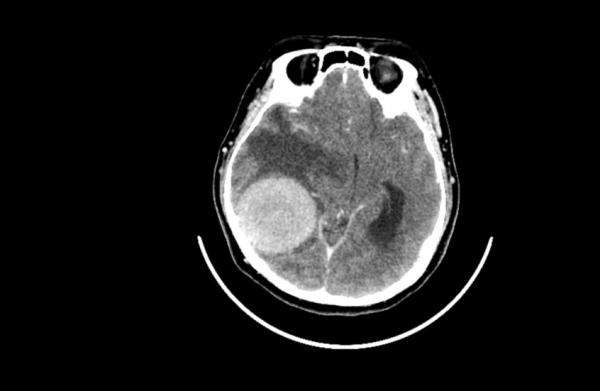

ويرتبط الورم الشفاني الدهليزي، أو كما يعرف أيضا باسم ورم العصب السمعي (وهو ورم حميد يصيب العصب المسؤول عن السمع والتوازن وينمو ببطء)، عادة بأعراض مثل فقدان السمع والطنين والدوار. لكن الدراسة الجديدة تكشف أن للعوامل النفسية دورا محوريا في شدة هذه الأعراض.